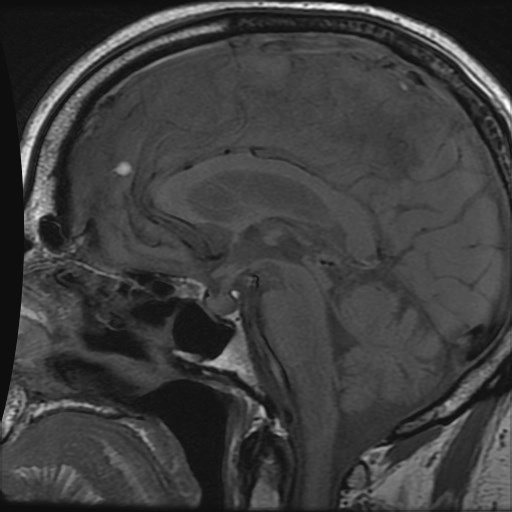

• Dày hộp sọ (Calvarial thickening)